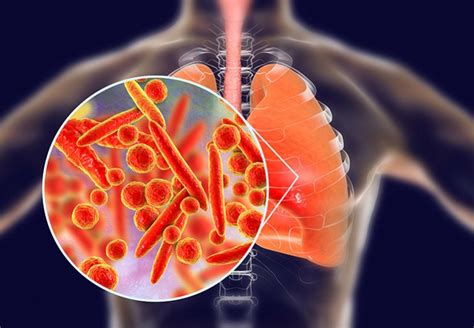

Komplexný sprievodca tabletkami na kašeľ pre deti. Zistite, ako rozlíšiť typy kašľa a vybrať najvhodnejší liek pre vaše dieťa.… Zobraziť viac